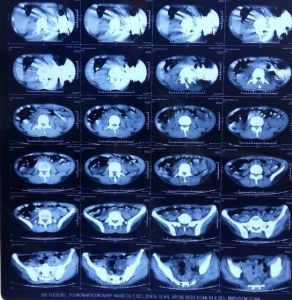

نيودلهي/سوا/ استخرج أطباء في مدينة هندية 40 سكينا من بطن مريض بعملية جراحية.

وذهب المريض إلى مستشفى مدينة أمريتسا شمال غربي الهند شاكيا من آلام مبرحة في بطنه الأسبوع الماضي.

وكان الرجل ابتلع السكاكين على مدى ثلاثة أشهر.

وقال الطبيب جاتيندر ماهوترا إن المريض لم يخبر الأطباء بعادته تلك، مشيرا إلى أن "الفحوصات بينت قيام الرجل بابتلاع السكاكين بارادته".

وأضاف "لم تكن العملية الجراحية سهلة وكان علينا الإعداد جيدا لضمان نجاحها دون ايذاء المريض".

واجرى العملية خمسة أطباء لكن المريض ما زال في مرحلة التعافي.